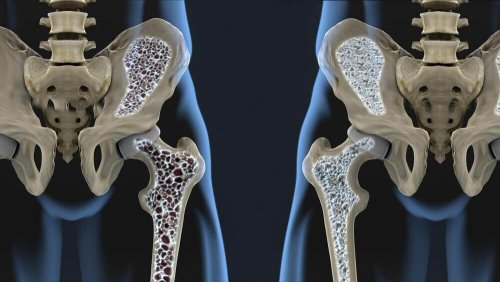

어떤 것들이 골다공증 예방에 도움이 될까? 누구나 자유롭게 움직이는 것을 사랑한다. 그러므로 골다공증을 미리 예방해야 한다. 아마 뼈에 칼슘이 좋다는 사실은 누구나 알고 있는 사실일 것이다. 골다공증을 예방하기 위해서는 칼슘 섭취가 필수적이다.

가까운 가족 중에 누군가 골다공증이 있다면 20대나 30대에 병원에 가서 검사를 받아보는 것이 좋다. 그리고 평소에 칼슘이 풍부한 음식을 챙겨 먹는 것도 좋다. 그래야 골밀도를 키울 수 있고, 퇴화가 빨리 진행되는 것을 막을 수 있다.

골다공증을 예방하기 위해서는 소금 섭취를 줄이는 것이 좋다. 소금이 뼈에 미치는 영향에 대해 발표된 연구가 아직 없긴 하지만, 고혈압이 있는 사람들은 골밀도 손실이 크다는 사실은 입증된 바 있다.

그리고 소금은 소변을 통해 배출되는 칼슘 양을 증가시킨다. 따라서 평소에 짜게 먹는 사람들은 뼈가 점점 얇아질 것이다.